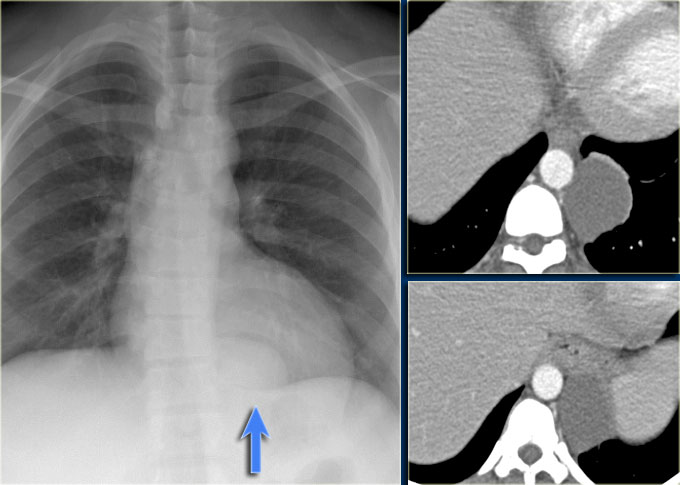

超声心动图诊断心脏转移性淋巴瘤 1 例_肿瘤_心包_心肌

图片尺寸586x433

呈蟹足样改变,可见血流信号)(图为患者影像检查结果:左侧腋窝淋巴结